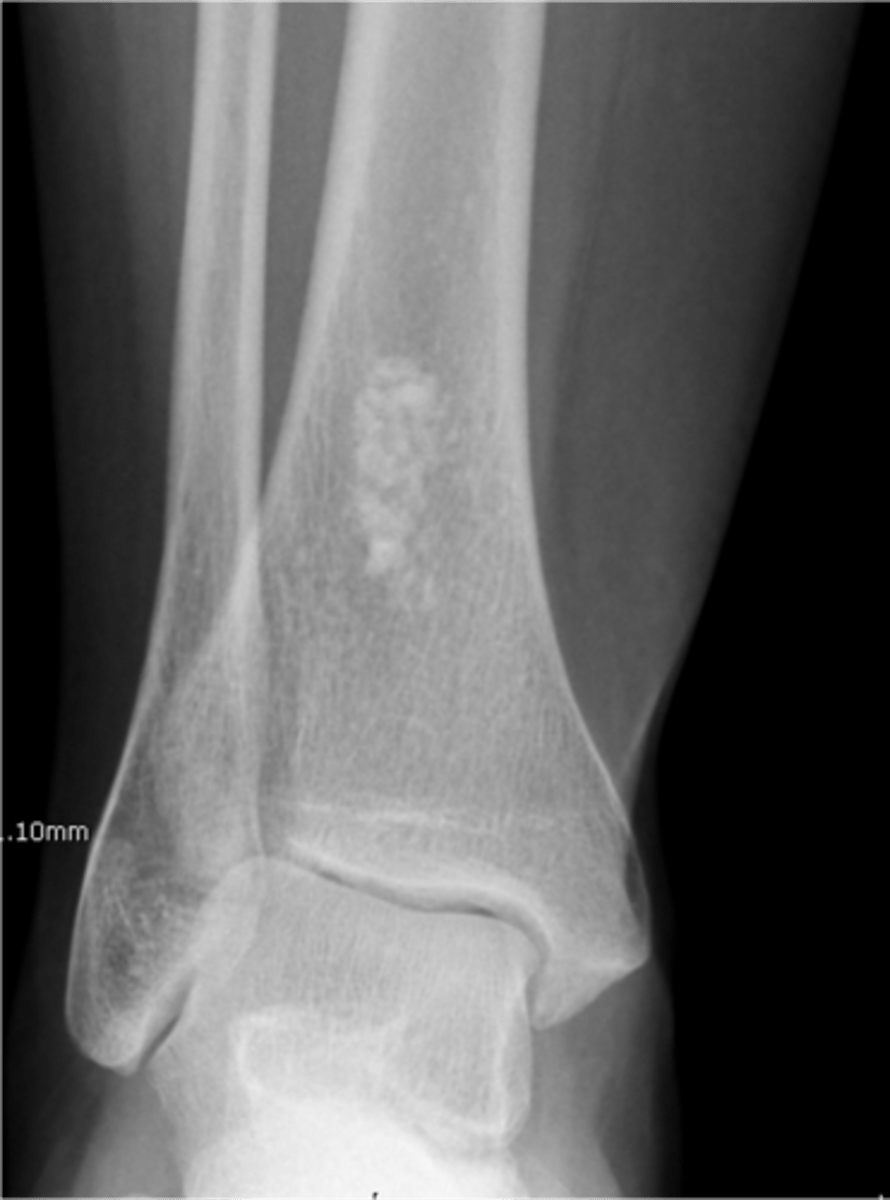

Intraosseous lipoma

- M=F

- 5-70 y.o.

- Asymptomatic

- Central target sequestrum

- Calcaneus

- Tibial metaphysis

- Fibular metaphysis

<p>- M=F</p><p>- 5-70 y.o.</p><p>- Asymptomatic</p><p>- Central target sequestrum</p><p>- Calcaneus</p><p>- Tibial metaphysis</p><p>- Fibular metaphysis</p>

70

New cards

Target sequestrum

ID sign of intraosseous lipoma

<p>ID sign of intraosseous lipoma</p>

71